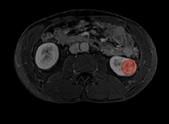

MRT des Bauchbereichs (Abdomendisgnostik)

• Niere

Nierentumor